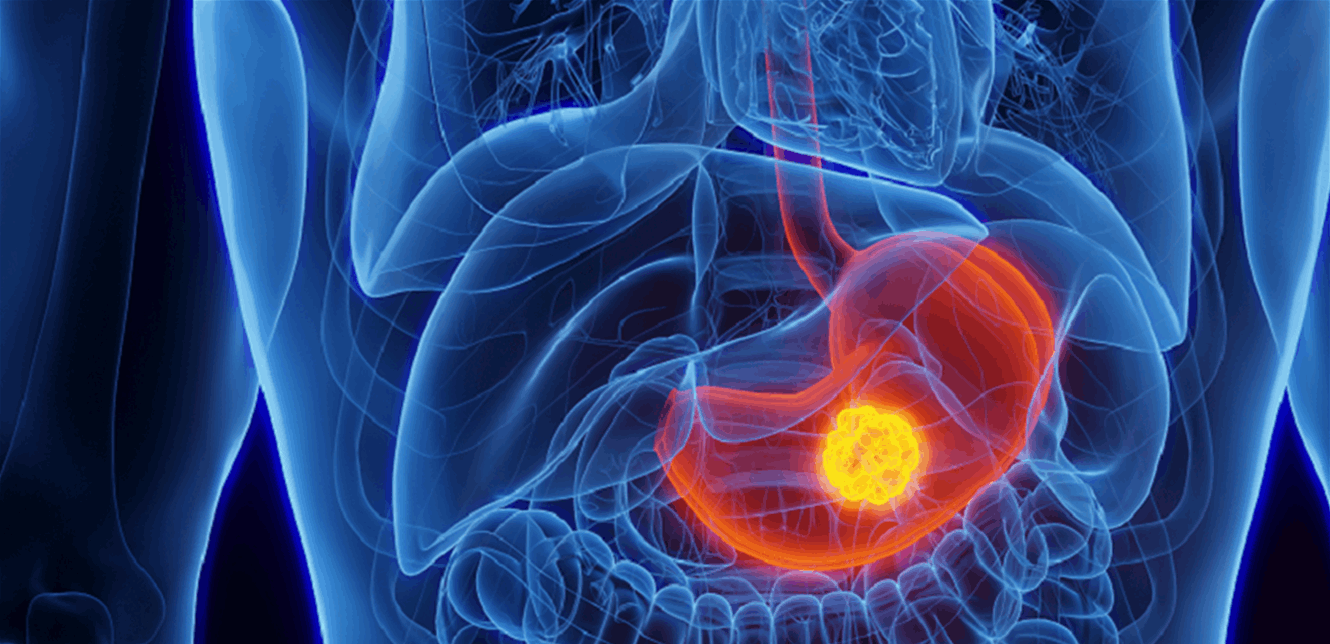

أثبت علماء من إيطاليا والبرازيل أن الإفراط في تناول الملح يزيد من خطر الإصابة بسرطان المعدة حتى بين الأشخاص الذين يتبعون نظاما غذائيا صحيا.

واكتشف الباحثون، أن تناول الأطعمة فائقة المعالجة (المشروبات الغازية ورقائق البطاطس والحلويات المصنعة) كان مرتبطا بزيادة خطر الإصابة بسرطان المعدة، وهو النوع الأكثر انتشارا من السرطان. وتشكل السكريات المضافة، التي تضاف أثناء معالجة هذه الأطعمة، ما بين 7-21 بالمئة من إجمالي المخاطر.

ولكن اتضح للباحثين أن الملح هو السبب الرئيسي لسرطان المعدة. ووفقا لهم أن الإفراط في تناول الصوديوم له تأثير ضار على بطانة المعدة، ويؤدي إلى الالتهاب وتفاعلات غير مرغوب فيها مع بكتيريا هيليكوباكتر بيلوري، التي توجد عادة في المعدة ويمكن أن تسبب التهاب المعدة.

ووفقا للباحثين، يمكن أن تسبب زيادة الصوديوم التهاب المعدة الضموري وتحول نسيجي- مضاعفات تنتج عن تهيج مزمن للغشاء المخاطي وتساهم في تطور السرطان. (روسيا اليوم)